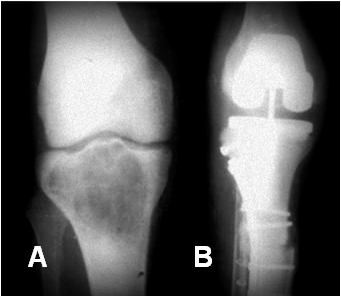

Fig 201 A. Cambios PostQx.

A: Rx AP. Lesión en la tibia, que corresponde a tumor de Ewing.

B: Rx AP. Resección de la lesión y colocación de material articulado.

Fig 201 B. Cambios PostQx.